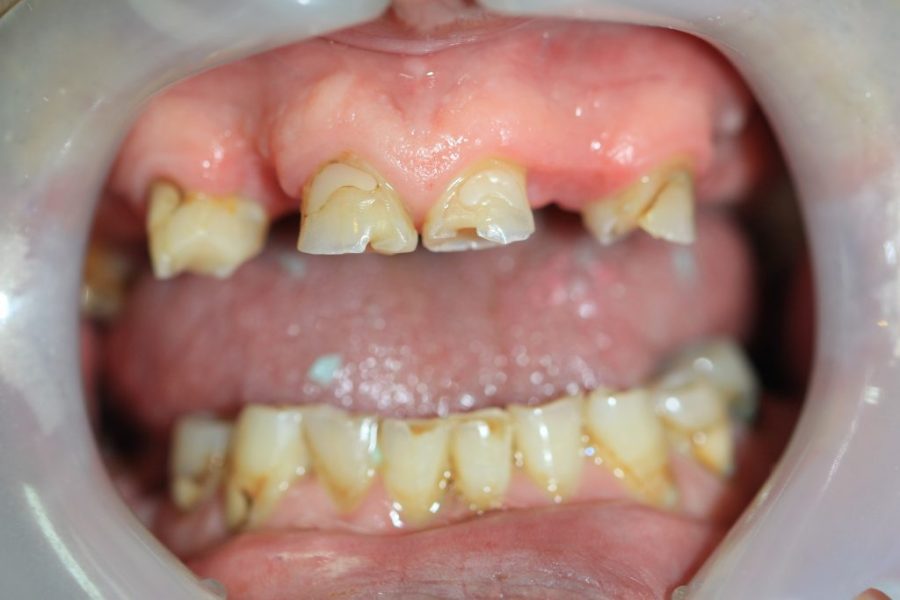

Henry’s Story: A Full Smile Makeover

Henry’s broken teeth were impacting his confidence. With a combination of root canal therapy, laser gum surgery, crowns, and dentures, we restored his smile over four weeks. Now, his family and grandchildren are thrilled with his transformation.